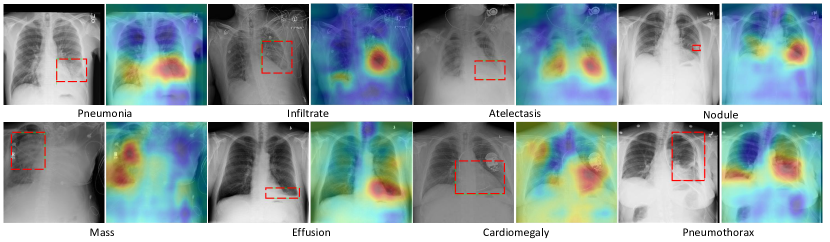

4.4. Localization of Lesion Regions

In Fig.4, we produce heat map to visualize the most indicative pathology areas on X-rays from evaluation subset, interpreting the representational power of network. Heat maps are constructed by computing the average of class-wise features after pooling along the channel dimension (Guan et al., 2018). We can see that our proposed network is able to localize lesion region on X-rays by assigning higher values than the normal. A visual evaluation has confirmed that the highlighted regions on X-rays are pretty close to ground-truth (red bounding boxes). Since our model did not use any bounding boxes in training, this has demonstrated that the proposed framework has a good interpretation ability in terms of localizing disease regions and can be widely applied in clinical practice where detailed annotations are hardly available.